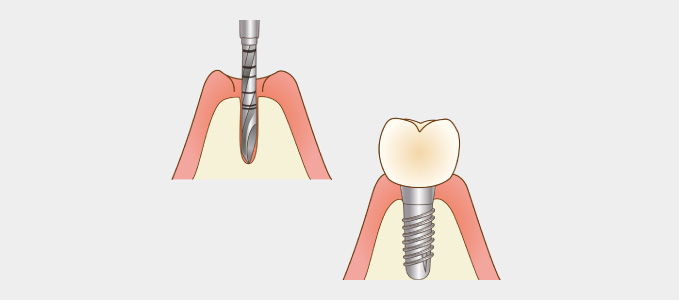

インプラント治療とは術前診査・診断を十分に行った上で、歯が抜けてしまった部分にインプラント(人工歯根)を埋め込み、その上から自然な見た目の人工歯を装着させるという治療法で、骨にしっかりとインプラント(人工歯)を定着させるため、自分の歯のようにしっかり、思い切り噛めるようになります。